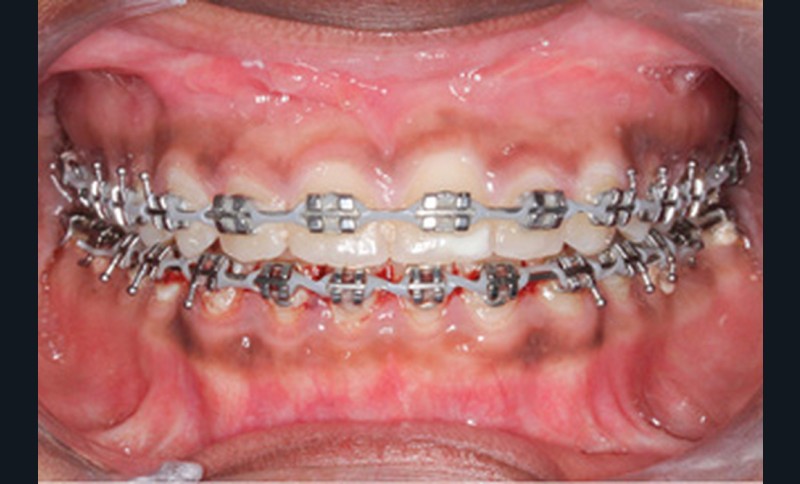

Un protocole ortho-chirurgical en chirurgie première a été retenu. Les étapes de traitement ont été les suivantes : motivation à l’hygiène bucco-dentaire et rééducation des fonctions, puis pose de l’appareil multi-attache edgewise conventionnel avec des arcs aciers .016x.022 passifs adaptés aux deux formes d’arcades, et enfin avancée de 6 mm et génioplastie d’avancée sur ces mêmes arcs.

Lors de la réévaluation post-chirurgicale, l’examen exo-buccal montre peu de changement, excepté l’occlusion et l’harmonie labiales retrouvées. Le surplomb et le recouvrement sont normalisés et le brossage amélioré. Les formes d’arcade sont concordantes, les médianes inter-incisives recentrées et les molaires et canines en classe I.